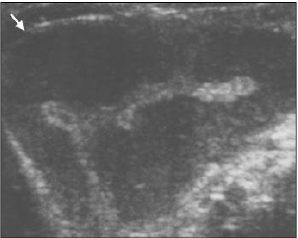

Assinale a hipótese diagnóstica mais provável para este caso.

“Estima-se que 10-18% das mulheres menopausadas assintomáticas tenham cistos ovarianos simples, e que 3% destas tenham cistos ovarianos complexos. Face à alta prevalência de cistos e à relativa baixa incidência (1 a cada 2.500 mulheres/ano) com câncer de ovário na população, há inúmeros estudos tentando identificar pacientes de maior risco.”

Assinale o método de escolha para avaliação de pacientes sintomáticas em que se suspeita de câncer ovariano.